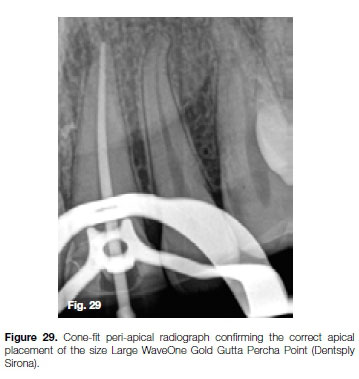

Having removed the fractured instrument, a size 30 K-File was fitted loose in the root canal up to working length as confirmed radiographically and with an electronic apex locator (ProPex, Dentsply, Sirona). According to the file selection criteria outlined by Van der Vyver et al. (2019)38 for WaveOne Gold files, a size large WaveOne Gold File (45/05) was selected for canal preparation.

After canal preparation and irrigation with heated 3.5% sodium hypochlorite and 17% EDTA solutions, a size Large WaveOne Gold Gutta Percha Point (Dentsply Sirona) was fitted and the position verified radiographically.

The canal was obturated with the selected gutta percha point and Pulp Canal Sealer (SybronEndo), using the continuous wave condensation technique with the Calamus Dual Obturation Unit (Dentsply Sirona).